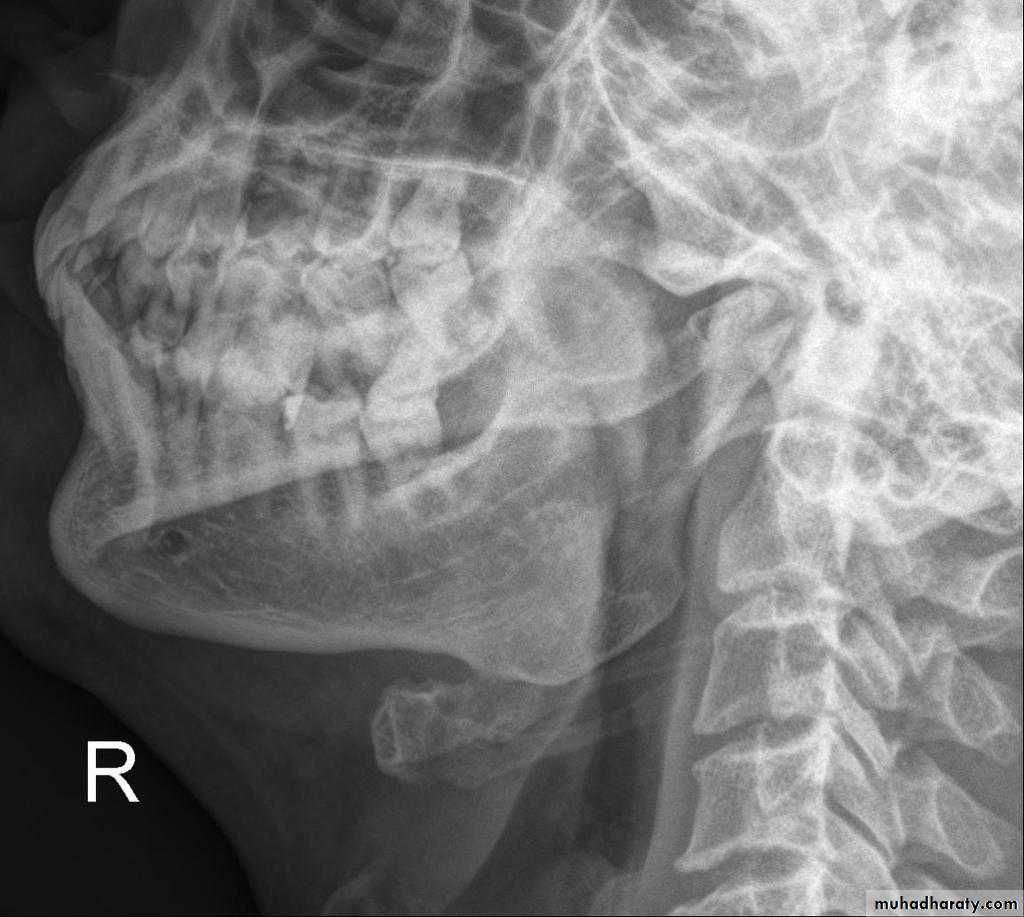

B. Extra oral (Postero-anterior "PA", Anteroposterior "AP", Cephalometric(true lateral), Oblique Lateral, Ocipito-mental, OPG, Submentovertex, TMJ View,etc.).